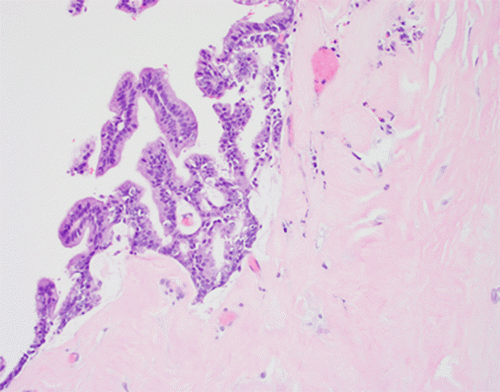

Figure 5. Histopathology of Pancreatic Neoplasm: Low-Grade Mucinous Carcinoma with Cribriforming. Published with Permission

H&E stain (20x original magnification) showcasing the neoplastic epithelium of the low-grade mucinous carcinoma. Note the presence of focal cribriform architecture (gland-in-gland formation) and the surrounding dense desmoplastic stroma

The final histopathological report of the primary tumor described a well-differentiated mucinous cystic neoplasm with an associated invasive adenocarcinoma (pancreatic ductal adenocarcinoma, PDAC) of the distal pancreas, without perineural or lymphovascular invasion. All other cytoreduction specimens (peritoneal and diaphragmatic stripping) contained acellular mucin with associated lymphohistiocytic inflammatory infiltrate. Microscopically, the pancreatic mass exhibited dissecting mucin pools derived from a low-grade mucinous carcinoma, associated with sparse cribriform epithelium, infiltrating ducts, and dense stroma (Figures 3-6).